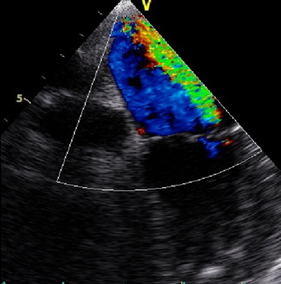

On the second day of her hospitalization, she had melena and gastroenterology adviced proton pump inhibitor. Her hemoglobin was 7.1 g/dL and 2 units of erythrocyte suspension were given. The patient had diffuse myalgia, palpitations and sinus tachycardia on electrocardiography. Her heart sounds were regular without murmur. During a physical examination, painless hemorrhagic cutaneous lesions were noted on her feet (Figure 1 [Fig. 1]). She was directed to cardiology and on echocardiography mild mitral regurgitation was noted. Transesophageal echocardiography (TEE) was planned in order to detect mitral regurgitation etiology. TEE showed mild mitral regurgitation and a vegetation on posterior mitral valve (Figure 2 [Fig. 2]). She was diagnosed with infective endocarditis and therapy was changed. Gentamicin (2x80 mg) plus ampicillin (4x3 gr) was started. On follow-up the patient still had fever, myalgia and discomfort. Two blood cultures revealed gram positive bacteria resistant to methicillin and the bacteria was identified as Staphylococcus aureus with BD Phoenix Automated Microbiology System. Also fluid sample (the fluid sample taken from her ankle) culture done in sheep blood agar revealed gram positive bacteria resistant to methicillin and the bacteria was identified as Staphylococcus aureus with BD Phoenix Automated Microbiology System. Both of the cultures’ isolates were resistant to methicillin and sefoxitine and susceptible to vancomycin, linezolid and teicoplanin. Although gentamicin plus vancomycin therapy was planned for the patient, vancomycin was not available so her therapy was changed to gentamicin (2x80 mg) plus linezolid (2x600 mg) according to culture antibiogram. The patient began to improve after medical therapy with linezolid and gentamicin. She had no fever anymore and her hemoglobin level was 9 g/dL. Blood urea and creatinine were in normal ranges 30 and 1 g/dL, respectively. In the third day her CRP-level began to decrease (20.1 mg/dL). Her CRP course was 12.6 mg/dL in the first week, 5.8 mg/dL in the second week, 3.2 mg/dL in the fourth week and 0.5 mg/dL in the sixth week. Control TEE showed mild to moderate mitral regurgitation and vegetation (Figure 3 [Fig. 3], Figure 4 [Fig. 4]). After six weeks of antibiotherapy (six week linezolid and two week gentamicin) she was free of infection and a control transthoracic echocardiography showed no mitral regurgitation or vegetation.

Figure 4: Mild to moderate mitral regurgitation